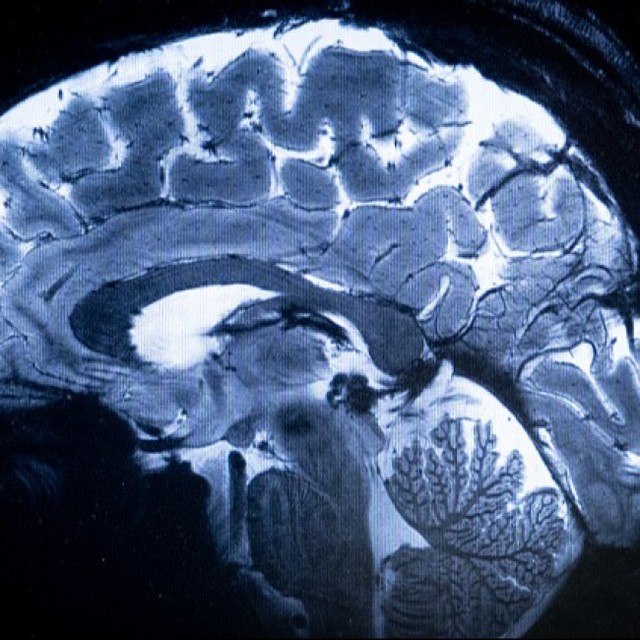

ドイツの研究で、2600人以上の成人のMRIスキャンを分析。親指が長い人ほど全体的に脳が大きい傾向にあることがわかった。PNAS誌に掲載された同研究は、多くの人が見過ごしがちな身体的特徴に、神経発達に関する手がかりがある可能性を示唆している。

脳容積が最も強く関連していたのは手の大きさそのものではなく、他の指に対する親指の比率であることがわかった今回の研究。この関連性は骨格成長に関わる遺伝子が幼少期の脳発達にも関与していることの反映と考えられている。